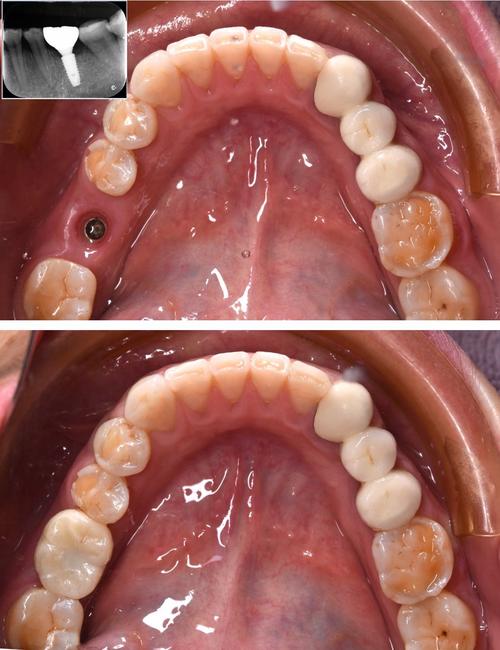

- 牙冠戴入后的效果对比图(缺牙前 vs 种植后)。

- 种植牙全景X光片,显示种植体在骨内的位置。